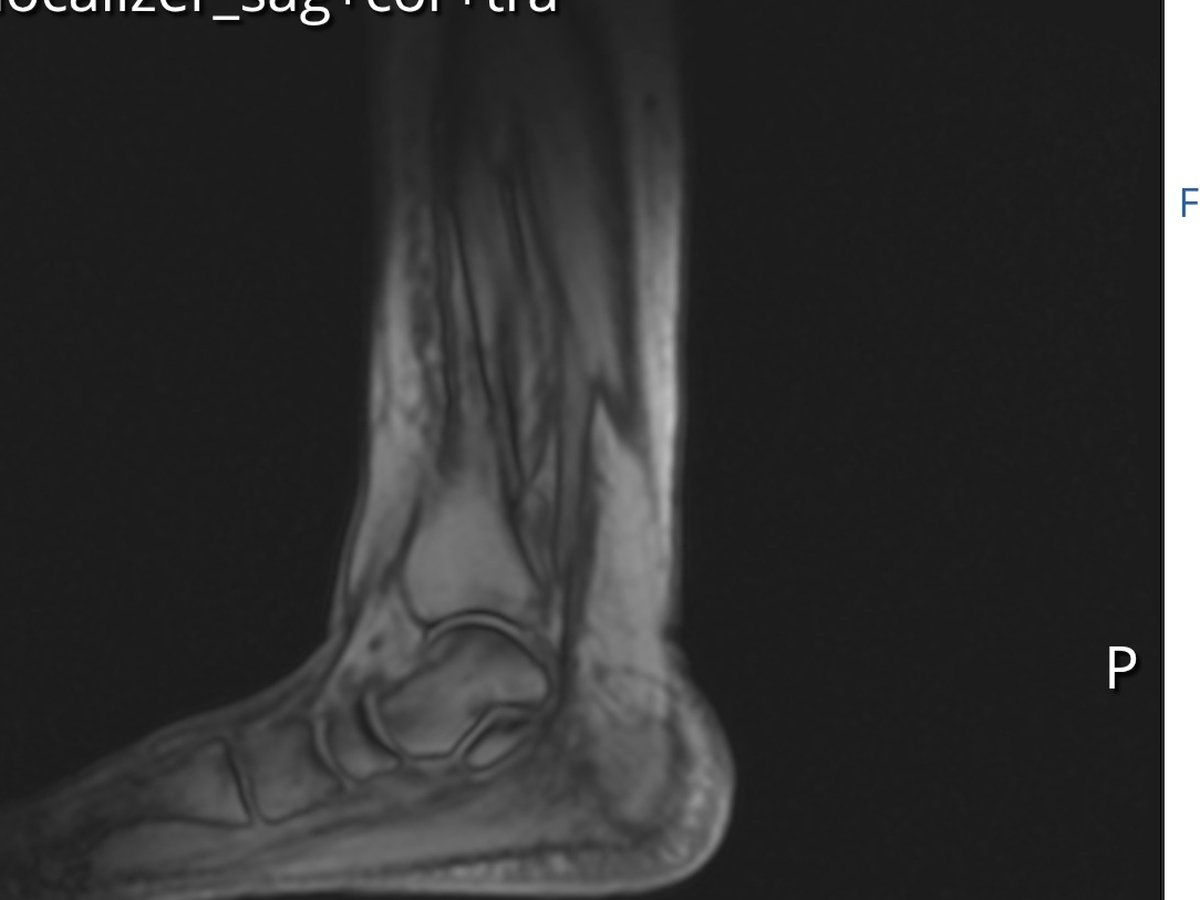

I have torn my posterior tibial tendon and even tho I've tried non surgical ways to heal it using braces and physical therapy, it has to be repaired surgically.